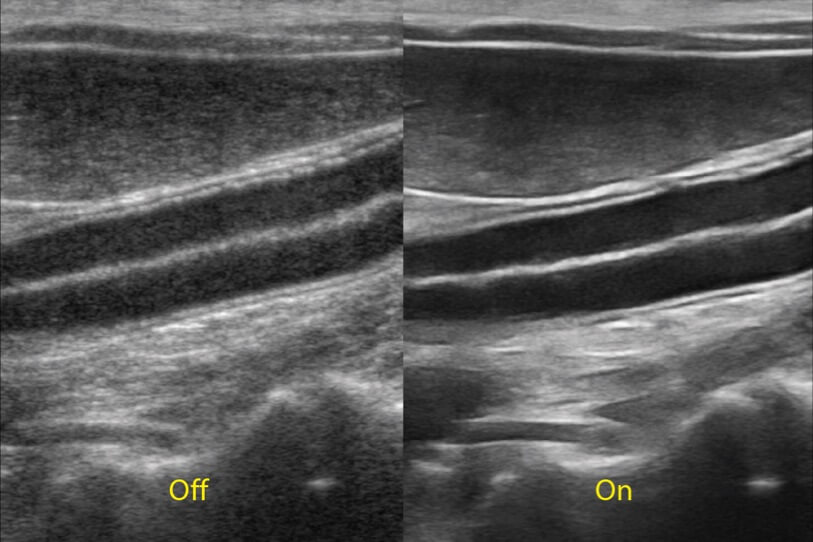

ProPet 70 進(jìn)一步提升了微米成像算法,更加注重對基礎(chǔ)原始圖像的還原和保留,在有效減少斑點(diǎn)噪聲、增強(qiáng)組織邊界顯示的同時(shí),避免過度優(yōu)化丟失真實(shí)的解剖信息。

為精細(xì)結(jié)構(gòu)及組織邊緣提供高清晰度的圖像和更大的成像視野。幫助減輕醫(yī)生的用眼疲勞,快速精準(zhǔn)獲得測量的數(shù)據(jù)。